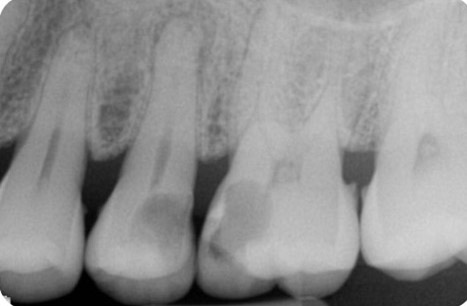

Endodontics is the study and treatment of disorders of the neurovascular tissue within the interior of teeth, including the pulp chamber and roots. These disorders occur most often when the root canal becomes infected as a result of extension of dental caries into the pulp chamber. With infection of the neurovascular tissue, necrosis can occur, and the disease process can progress to involve the entire root canal system (Figure 1). Pain, often intense, will be experienced by the affected individual. As necrotic debris becomes located at the apex of the root in the alveolar bone, the infection can extend beyond the local area to include the more coronal periodontal tissues (Figure 2). Obvious clinical swelling and suppuration can be present. The bacteria that characterize these acute lesions are Gram-negative anaerobes. These infections can be associated with systemic symptoms, including fever and malaise.

Figure 1. Radiograph demonstrating extensive caries of the distal half of the maxillary second bicuspid and mesial half of the maxillary first molar. Apical periodontitis is clearly visible for the second bicuspid and widening of the apical area of the roots of the first molar is suggested. Radiograph courtesy of Drs. Y. Berlin-Brenner and L. Levin.